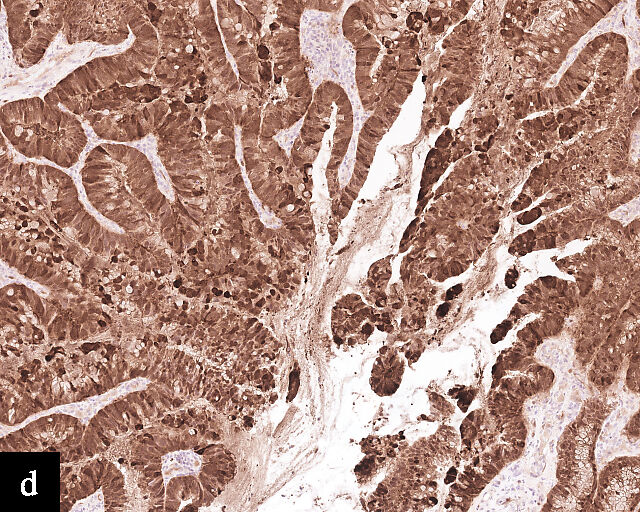

2

Histological sections of HPV-independent cervical carcinomas. (a) Clear cell adenocarcinoma. (b) Endometrioid adenocarcinoma. (c) Well-differentiated gastric-type adenocarcinoma. (d) Poorly differentiated gastric-type adenocarcinoma. H&E stain. Magnification ×20.

Clear cell adenocarcinomas of the cervix follow a bimodal age distribution. The first peak is observed at late adolescence/early adulthood13,14 and is associated with in-utero exposure to diethylstilbestrol (DES). The median age at presentation for clear cell adenocarcinoma not related to DES exposure is 48 years15 and constitutes the second peak. Its histological appearance resembles that of clear cell adenocarcinomas from other parts of the female genital tract (uterine corpus and ovaries), in particular tumor cells displaying overt nuclear atypia and a characteristic clear cytoplasm, arranged in variable destructive growth patterns16 (Figure 2a). Clear cell adenocarcinomas of the cervix share common immunophenotypic features with upper female genital tract carcinomas, notably PAX8 positivity and non-diffuse p16 expression17 (Figure 3a,b). Limited data from case series indicate that mutations in CMTM5 and WWTR1 are relatively frequently detected in clear cell adenocarcinomas of the cervix.18,19

Gastric-type adenocarcinomas frequently present at a late stage (parametrial involvement, ovarian and lymph node metastasis) with unfavorable histopathological features (lymphovascular invasion and positive peritoneal cytology) and significantly worse disease-free and overall survival compared to HPV-associated endocervical adenocarcinomas.24 Macroscopically, these tumors have been associated with a ‘barrel-shaped’ cervix, attributed to deep invasion and induction of desmoplasia, leading to diffuse enlargement and thickening of the cervix.25 The histological appearance of these tumors is diverse. Well-differentiated forms (Figure 2c) can be difficult to distinguish from non-lesional cervical glands, which is reflected in the older terminology ‘adenoma malignum’ and ‘minimal deviation adenocarcinoma’. These historically referred to gastric-type adenocarcinomas that exhibit bland morphological features.22 In contract, poorly differentiated tumors can display variable architectural patterns, ranging from irregular incomplete, glands to solid nests or single cells in which glandular differentiation is not readily evident26 (Figure 2d).